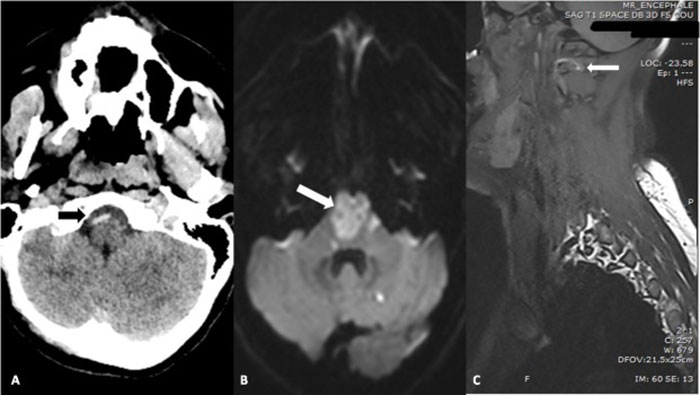

Image credits: National Library of Medicine